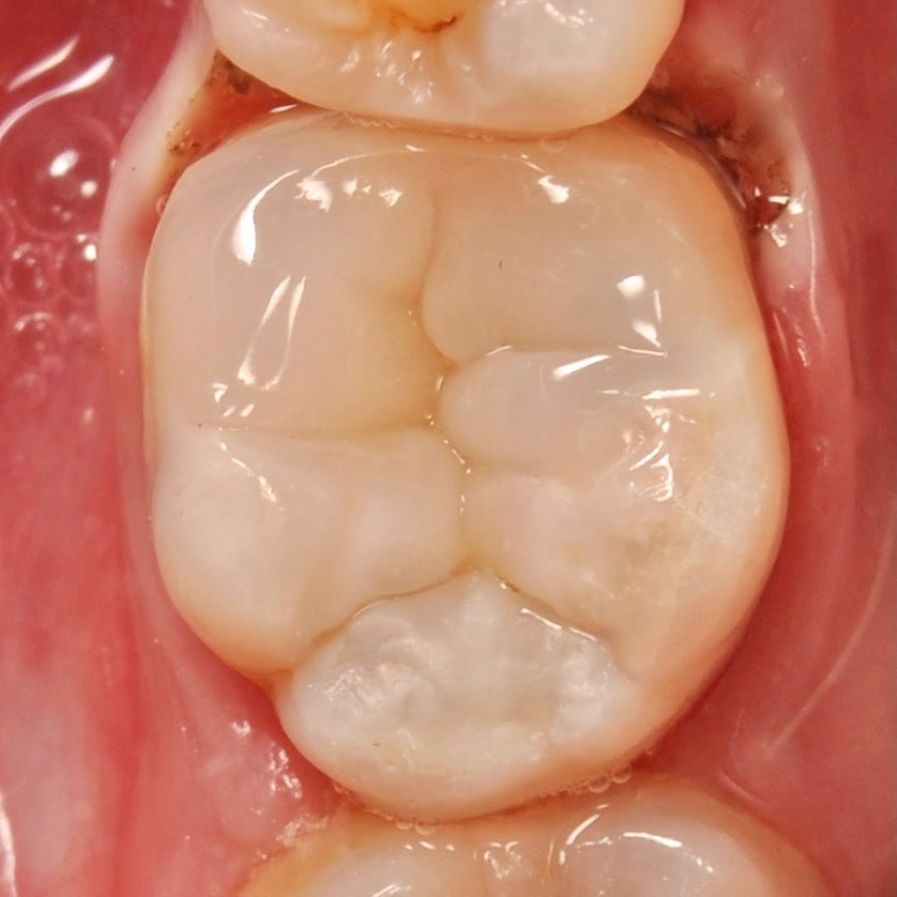

зуб с обработанными каналами

Лечения пульпита

Устранить инфекцию - спасти зуб

Каналы наших зубов можно представить как дерево имеющее множество ответвлений. Задача врача провести их обработку сохранив ткани зуба.